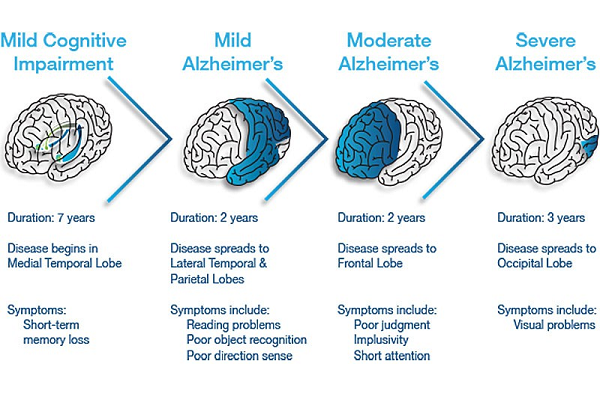

Embrace seasonal changes with our predicting alzheimers disease progression using a versatile sequence gallery of countless weather-themed images. highlighting time-sensitive blue, green, and yellow. perfect for seasonal marketing and campaigns. Each predicting alzheimers disease progression using a versatile sequence image is carefully selected for superior visual impact and professional quality. Suitable for various applications including web design, social media, personal projects, and digital content creation All predicting alzheimers disease progression using a versatile sequence images are available in high resolution with professional-grade quality, optimized for both digital and print applications, and include comprehensive metadata for easy organization and usage. Explore the versatility of our predicting alzheimers disease progression using a versatile sequence collection for various creative and professional projects. Advanced search capabilities make finding the perfect predicting alzheimers disease progression using a versatile sequence image effortless and efficient. Diverse style options within the predicting alzheimers disease progression using a versatile sequence collection suit various aesthetic preferences. Time-saving browsing features help users locate ideal predicting alzheimers disease progression using a versatile sequence images quickly. Regular updates keep the predicting alzheimers disease progression using a versatile sequence collection current with contemporary trends and styles. Reliable customer support ensures smooth experience throughout the predicting alzheimers disease progression using a versatile sequence selection process.